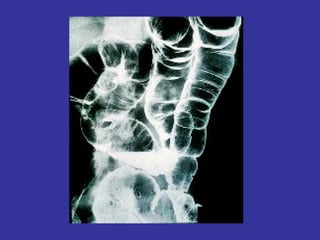

•   Estudios de imágenes: Rx tórax, Rx colon a doble

contraste, ecografía abd., TAC abd. Eco-endorrectal.